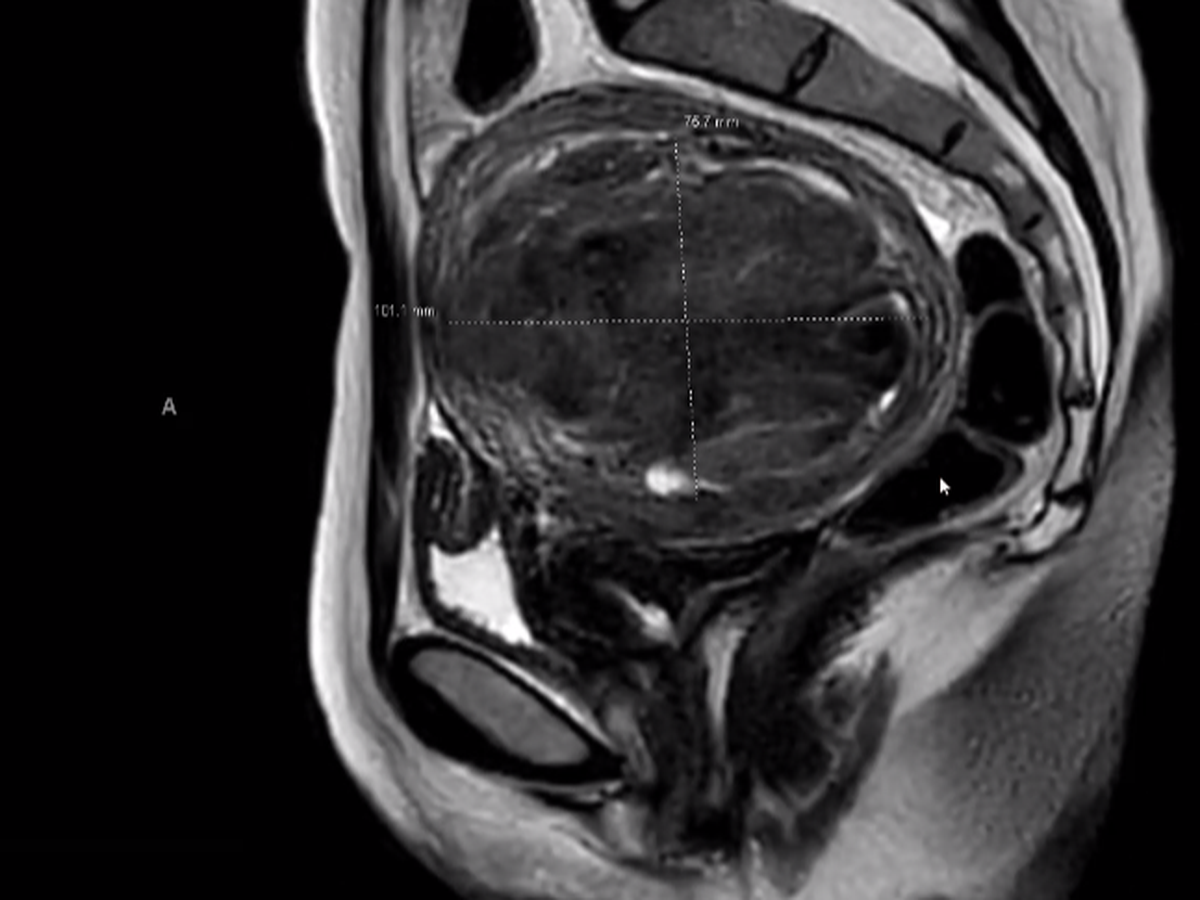

It’s difficult to sit down and write this- with fear of publicly sharing such an intimate health issue, and shame in asking for help when there are so many other people needing financial assistance within the current climate. On March 17th I’ll have a 12cm fibroid removed from my uterus. Due to the size of the fibroid (anything beyond 10cm is considered large, the size of a grapefruit) it will be removed via abdominal myomectomy. The goal of the abdominal myomectomy is to preserve the health of my uterus and avoid a full hysterectomy.

The following months have been a rollercoaster of learning about my body through followup ultrasounds, OBGYN appointments, meeting with a laparoscopic surgeon, then being referred to a myomectomy surgeon, having an MRI, blood tests, and iron infusions (to reduce the risk of a blood transfusion during surgery). Because of the size of the fibroid it can not be removed laparoscopically and thus the recovery time will be significantly longer, 4-6 weeks. I’m asking for financial assistance to help cover the burden of already taking off so many days for preliminarily doctors appointments/surgical planning, as well as the month+ I’ll have to take off to heal from the surgery. Truly anything helps. If you’ve read this far I love you, thank you for caring. If you’re unable to donate but still want to help I would appreciate any meal dropoffs, book loans, handwritten poems, movie recommendations or just hello’s. Thank you again for reading xx